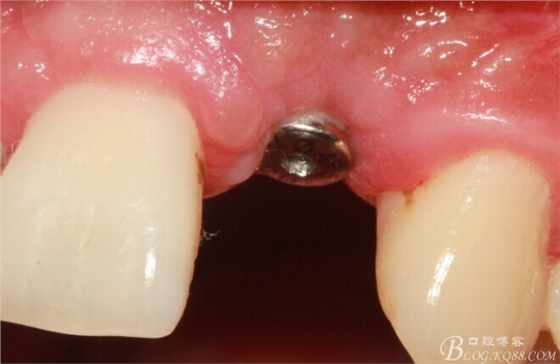

術(shù)后5個(gè)月。